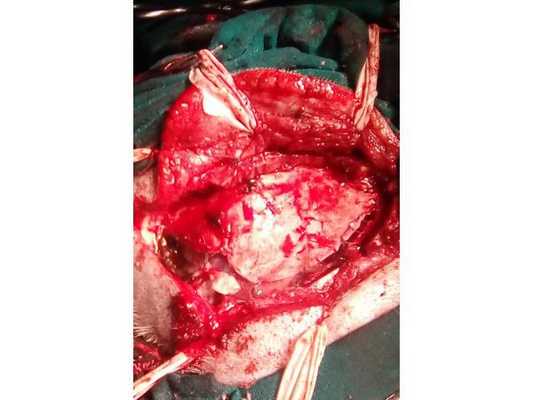

Больному произведено одномоментное удаление каверномы правой лобной доли и субдуральной гематомы.

Ход операции. Из полуовального разреза мягких тканей в правой лобно-височной области произведена костно-пластическая трепанация. Твердая мозговая оболочка (ТМО) напряжена, не пульсирует, имеет темную окраску. Она вскрыта крестообразно. В момент вскрытия ТМО в рану излилась жидкая часть гематомы красно-коричневого цвета. Под ТМО обнаружена плотная часть гематомы, представленная темными сгустками. Сгустки удалены обычным отсосом, после чего в проекции верхней лобной борозды обнаружена типичная ткань каверномы. В месте выхода на кору мозга кавернома интимно спаяна со сгустками крови, что свидетельствовало о том, что она явилась источником кровоизлияния. С помощью обычного отсоса, отмыванием физраствором и перекисью водорода удалены сгустки крови из-под ТМО в лобной, теменной и височной областях. Кавернома отделялась от мозга по перифокальной зоне, представленной глиозом. Она удалена единым блоком, после чего образовалась полость 1×2 см. Осуществлен тщательный гемостаз с помощью гемостатической марли и коагуляции. Мозг расправился, появилась четкая пульсация. ТМО зашита наглухо. Костный лоскут уложен на место и фиксирован лигатурными швами. Послойно зашиты мягкие ткани.

Субдуральная гематома удалена. В нижнем углу оперативного доступа визуализирована сосудистая мальформация

Пациент взят на операцию: ⠀•⠀Выполнен дугообразный разрез мягких тканей в правой лобно-височно-теменной области. Скелетирована кость. ⠀•⠀Наложены два фрезевых отверстия, из которых краниотомом выпилен костный лоскут 6,0*8,0 см. ⠀•⠀Произведён гемостаз моно- и биполярной коагуляцией, воском по ходу доступа. ⠀•⠀Твёрдая мозговая оболочка вскрыта подковообразно. Визуализирована субдуральная гематома, представленная плотными сгустками тёмно-вишнёвого цвета (рис. 3). ⠀•⠀Начато удаление сгустков путём аспирации и отмыванием физиологическим раствором. Общий объём субдуральной гематомы около 120 мл. Признаков черепно-мозговой травмы (кортикальных очагов ушиба, травматического субарахноидального кровоизлияния, гиперемии, отёка головного мозга) нет. ⠀•⠀При удалении сгустков с конвекситальной поверхности лобной доли открылось интенсивное венозное кровотечение. С целью доступа к источнику кровотечения разрез мягких тканей продолжен в конвекситальном направлении и краниотомом выпилены два дополнительных костных лоскута (из-за интенсивности кровотечения найти локализацию источника было затруднительно). ⠀•⠀Визуализировано кровоточащее образование, сращённое с твёрдой мозговой оболочкой и корой головного мозга, по виду — сосудистая мальформация (рис. 4). ⠀•⠀Гемостаз подходящих сосудов и самого образования выполнен последовательной биполярной коагуляцией (рис. 5: сосудистая мальформация указана наконечником аспиратора). ⠀•⠀Кровотечение остановлено. Мозг расправился, пульсирует. Твёрдая мозговая оболочка ушита викрилом с одновременным подшиванием по периметру трепанационного окна (рис. 6). ⠀•⠀Дефекты твёрдой мозговой оболочки и сосудистая мальформация укрыты гемостатической губкой (рис. 7). ⠀•⠀Костные лоскуты уложены на место (рис. 8). ⠀•⠀Послойный шов раны выполнен викрилом и капроном. ⠀•⠀Кожа ушита обвивным швом по Мультановскому. Ретроспективно на фронтальной ангиограмме можно заподозрить сосудистую мальформацию, ставшую источником гематомы (рис. 9). На девятые сутки после операции для обеспечения проходимости дыхательных путей, проведения длительной искусственной вентиляции лёгких, облегчения санации трахеи и бронхов пациенту выполнена нижняя трахеостомия по Бьёрку.